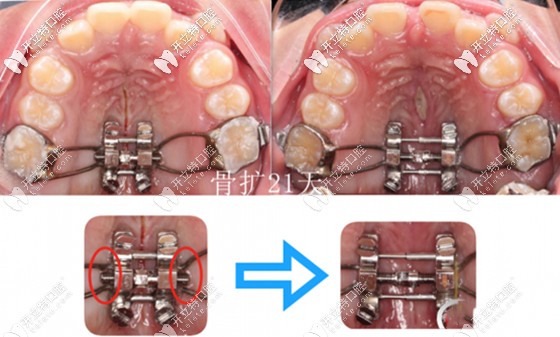

而根據(jù)其擴(kuò)大牙弓的速度不同,可分為快速擴(kuò)弓(周擴(kuò)弓范圍在1.4~3.5㎜)和慢速擴(kuò)弓(周擴(kuò)弓范圍在0. 4~1.2毫米)兩大類。

重點(diǎn)是:快速擴(kuò)弓一般適用于頜面骨骼處于生長發(fā)育期的兒童;而慢速擴(kuò)弓適用于生長發(fā)育已接近完成的大齡青年。

牙齒擴(kuò)弓矯正前后效果對(duì)比圖